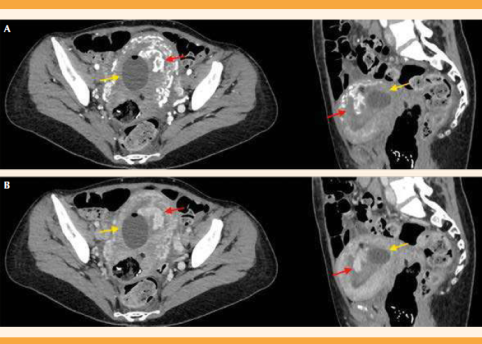

Al día siguiente, luego de conseguir la estabilización, se practicó un tomografía abdominal con contraste intravenoso (Figura 1) en la que se objetivó que el útero estaba aumentado de tamaño con moderados signos de hipervascularización miometrial, predominantes en la pared posterior y un área focal pseudonodular en las estructuras vasculares de mayor calibre, en la cavidad endometrial de 4.5 x 3.6 x 3.9 cm, sin signos de sangrado activo. Todo ello parecía indicar que se trataba de una malformación arteriovenosa uterina adquirida luego de un procedimiento de radiofrecuencia para ablación de un mioma uterino, y que había sido la causa de la hemorragia puerperal inmediata y tardía.

Figura 1 Tomografía axial computada con contraste intravenoso. A. Cortes axial y sagital en fase arterial. B. Cortes axial y sagital en fase venosa, la flecha roja señala el área vascular de mayor calibre en la cavidad endometrial, con sonda de Foley (flecha amarilla) adyacente.